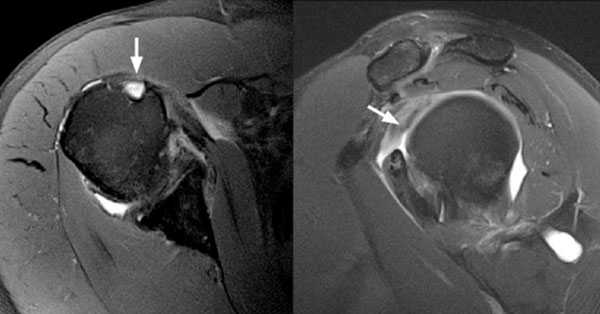

Рис.3 МРТ-картина разрыва сухожилия длинной головки бицепса

На МРТ диагноз отрыва дистального сухожилия двуглавой мышцы плеча был подтверждён. На представленных выше снимках отчётливо визуализируется оторванное сухожилие двуглавой мышцы плеча.